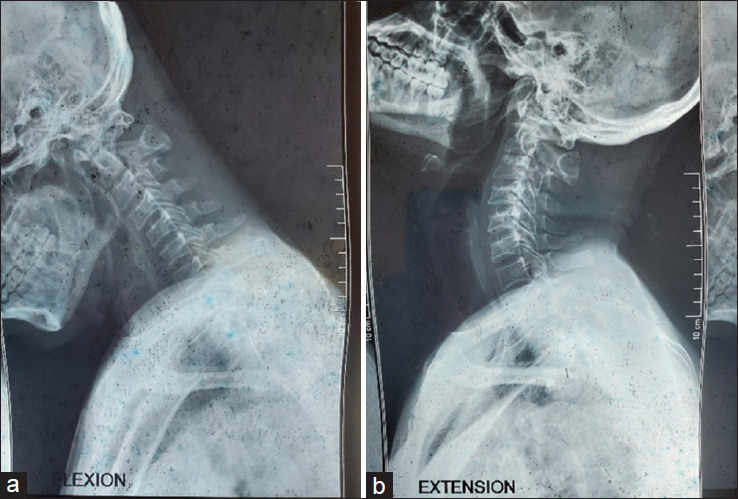

The shunting system has been generally recognized for the treatment of syringomyelia. However, recent publication has documented the role of atlantoaxial stabilization in the treatment of this condition. The objective is to present a case report highlighting our experience in the management of syringobulbia and syringomyelia in an adult male. We present a 45-year-old male who presented with an inability to walk with associated bladder and bowel symptoms. Neuroradiological studies of the brain and the whole spine revealed an extensive syringomyelia extending from the medulla oblongata to the T12 thoracic spinal level. There was no obvious focal mass lesion or bony lesion, and there were no anatomic features suggestive of Chiari I malformation. A management decision was challenging in this case. Atlantoaxial stabilization was considered based on Atul Goel's philosophy that the basic pathology in syringomyelia is C1/C2 instability, and that treatment is C1-C2 fixation. Intraoperative findings confirmed atlantoaxial instability from the direct bone handling during the procedure. There was immediate postoperative improvement in his motor function, which remained sustained, with free and brisk active mobilization at 3 months follow-up. Neuroimaging performed at 14 month's postsurgery revealed a reduction in the size of the syrinx cavity. This single and first experience of atlantoaxial stabilization for the treatment of syringomyelia in our environment may support the assertion by Goel that atlantoaxial instability is the pathology in syringomyelia, and atlantoaxial fixation should be a therapeutic consideration.